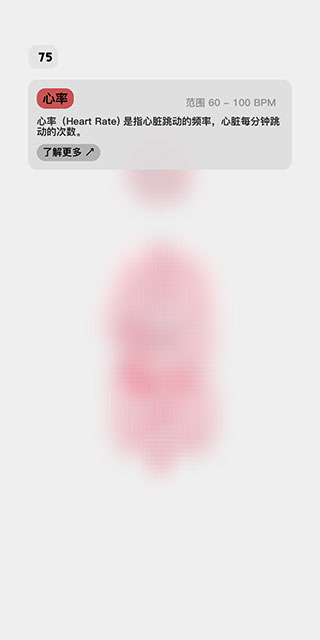

3、任意点击其中的一个指标,会显示该指标的说明信息和正常范围,点击下方的了解更多按钮,会打开浏览器,跳转到更详细的科普说明页面。